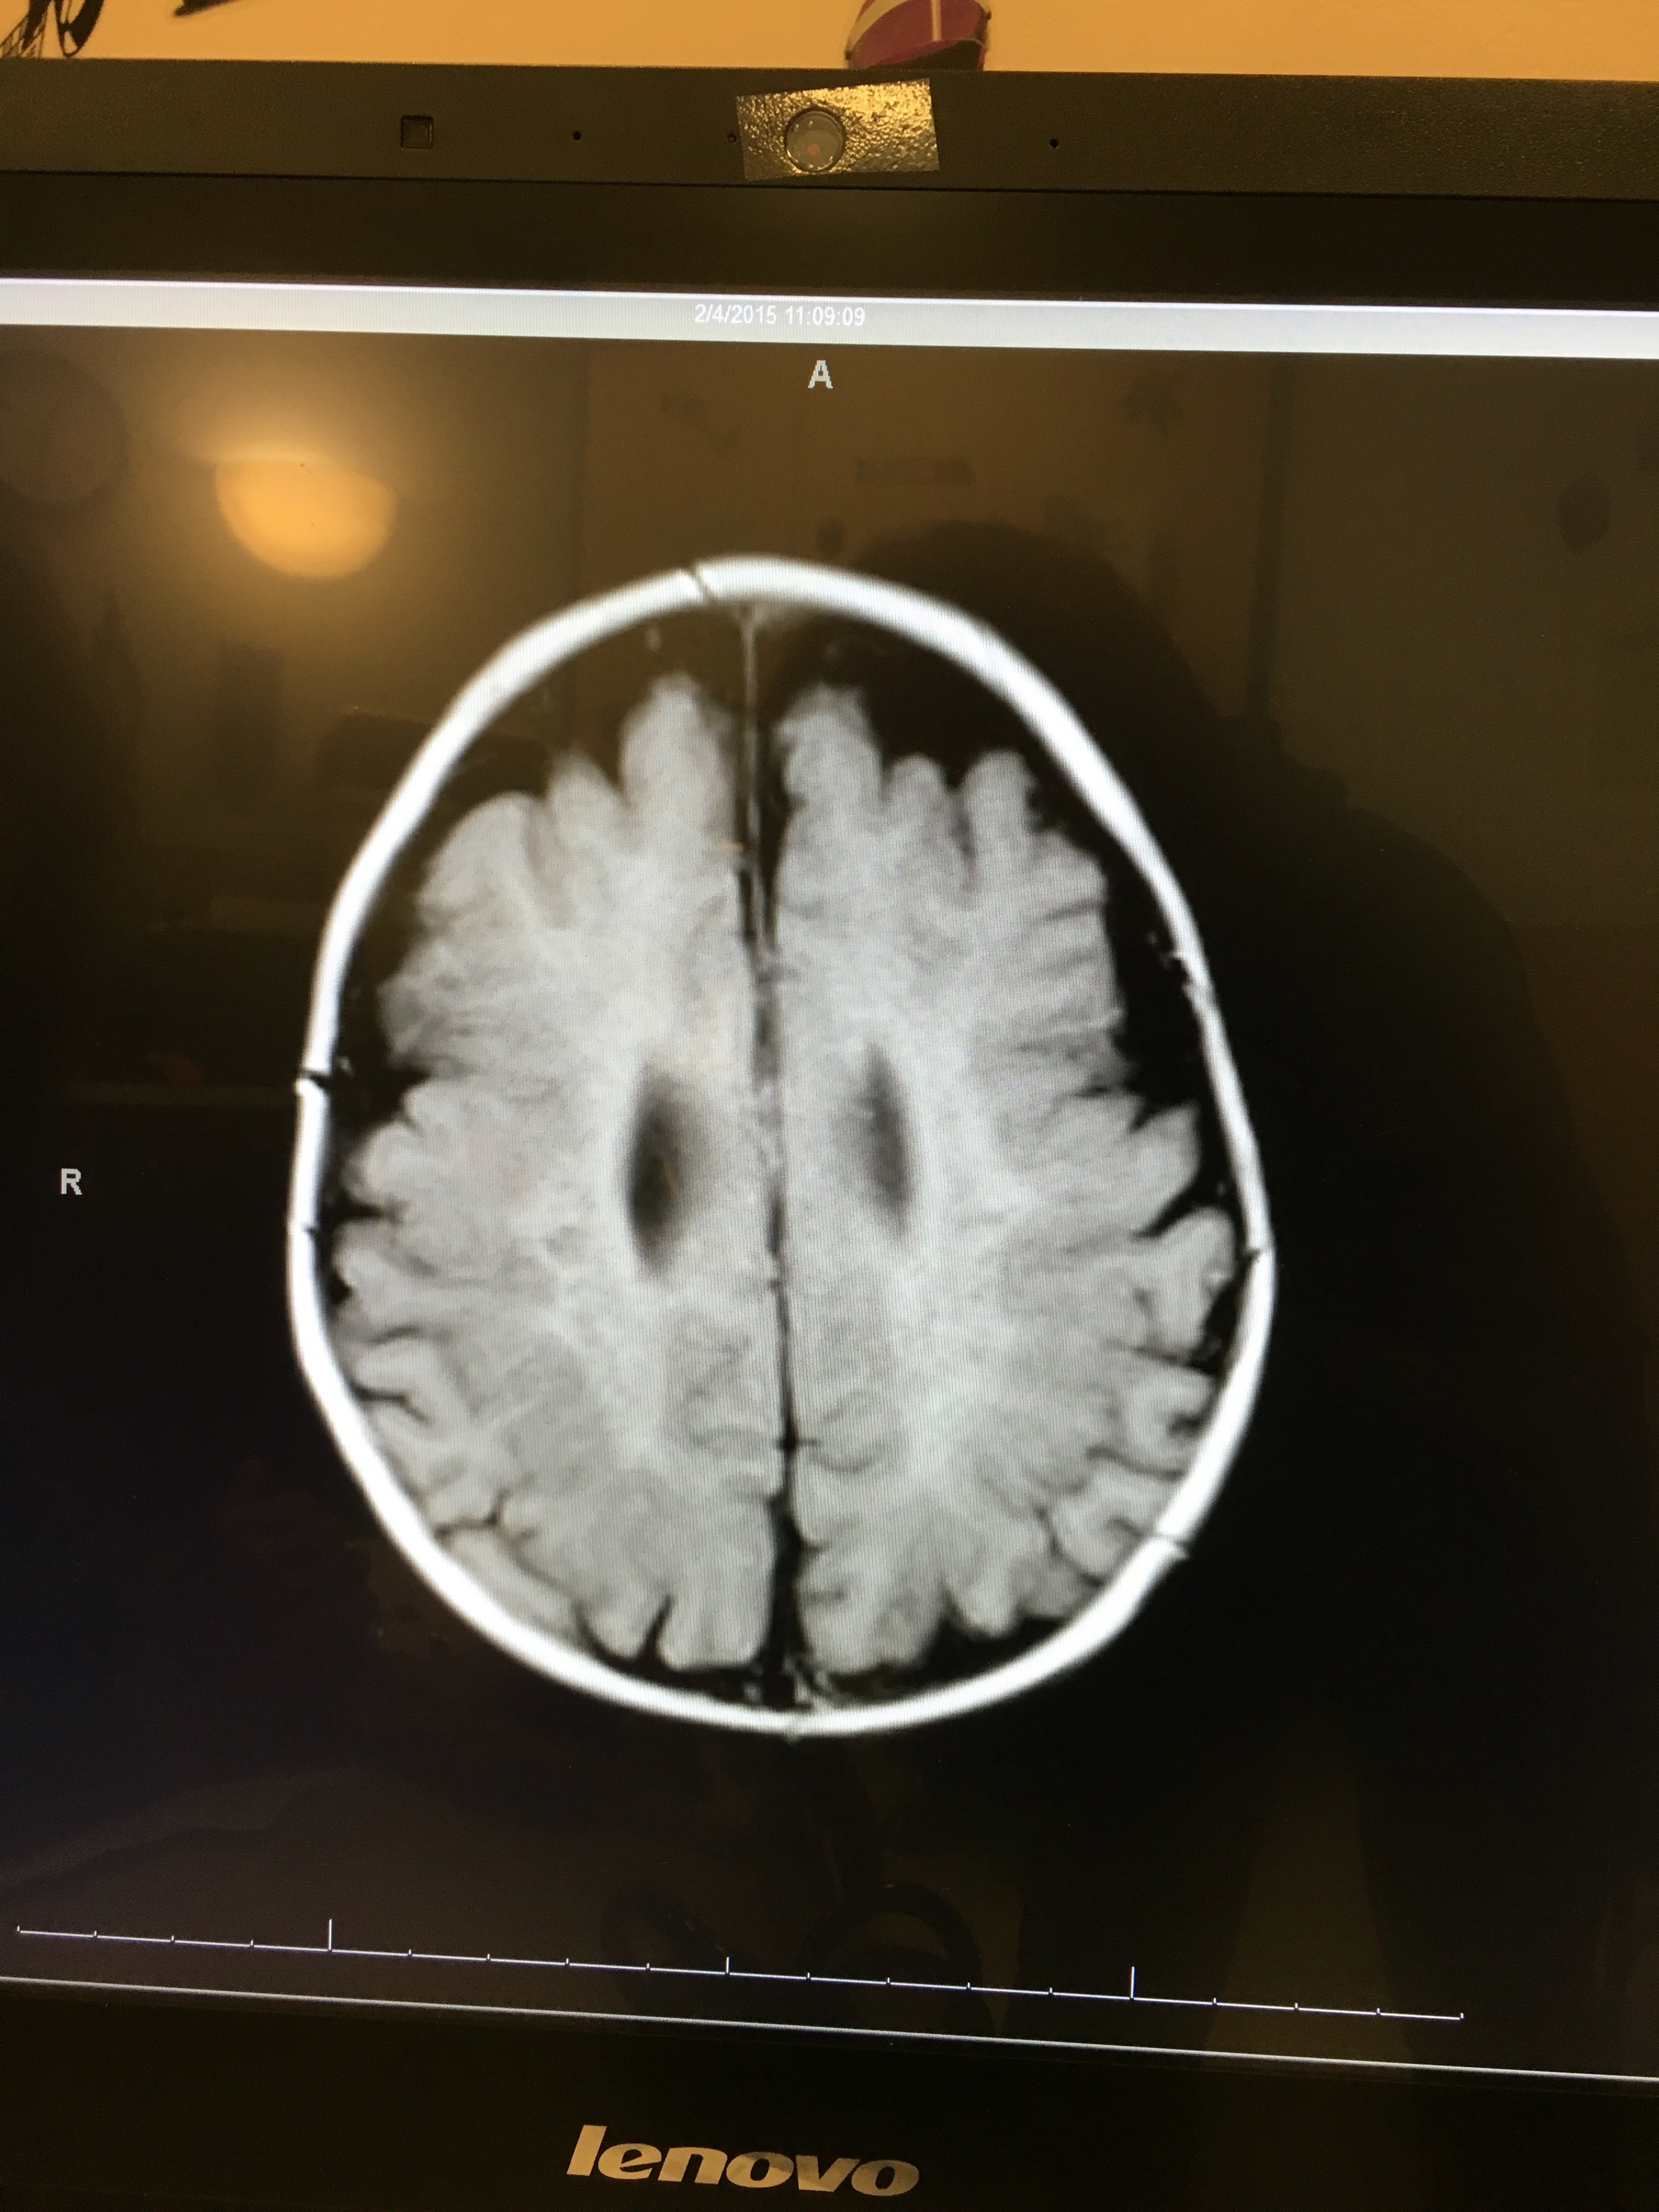

Tori’s first MRI was one year ago today.

We didn’t see the images of the MRI (or learn in detail about what they saw) until February 6th, but I want to include them in this post.

We have never shared these publicly.

Here are two screenshots of Tori’s brain on February 4, 2015.

We knew then that something was seriously wrong, even from our medically-untrained perspective.